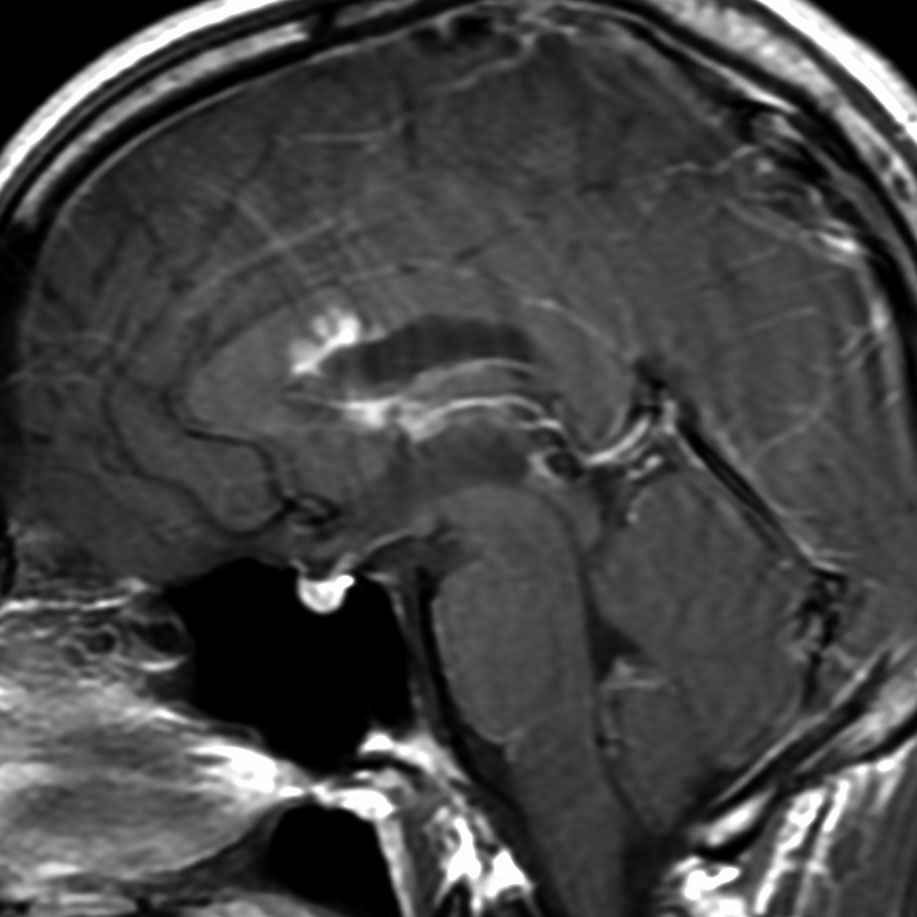

ガドリニウム増強では,前頭葉腫瘍というより,側脳室壁にベトベトくっついているような腫瘍です。germinoma特有のsubependymal infiltration像を示します。

生検後2ヶ月,セカンドオピニオンのために受診された時の画像です。腫瘍が縮小傾向にあります。入院中に行われた何度かのCT被曝の影響で,germinomaの退縮が生じたのだと判断しました。

左はICE化学療法 (IFO/CDDP/VP-16)前,右は1コース終了後です。腫瘍は顕著に縮小してgerminomaとして普通の化学療法反応性を示します。また,松果体と下垂体には腫瘍はありません。